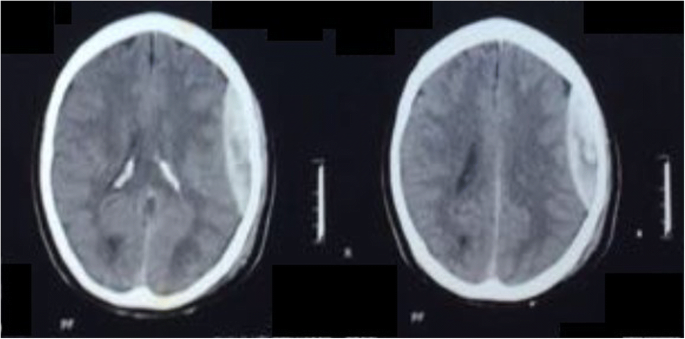

Extradural haematoma